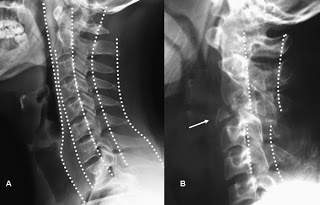

A) Radiografía lateral normal de columna cervical, con las 5 líneas que pueden trazarse sobre ella. B) Fractura en lágrima por mecanismo de flexión de C3. El fragmento en lágrima se aprecia anterior (flecha). Posteriormente se observa disrupción de la línea vertebral posterior y espinolaminar en un paciente tetrapléjico.Curva ‘rectificada’ por Latigazo cervical